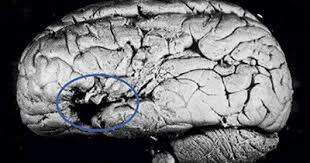

• Paul Broca

Paul Broca

Falleció un paciente que había sufrido pérdida del lenguaje y que era objeto de estudio. El examen postmortem demostró que el enfermo presentaba una lesión grave en la zona frontal posterior.

• AFEMIA

AFEMIA

Cuando un paciente perdía el habla, la patología se localizaba en el hemisferio izquierdo, en tanto que las lesiones que afectaban la misma región del hemisferio derecho no producían la pérdida de la capacidad lingüística. “La afemia se relaciona con lesiones de la tercera circunvolución frontal del hemisferio izquierdo del cerebro”.